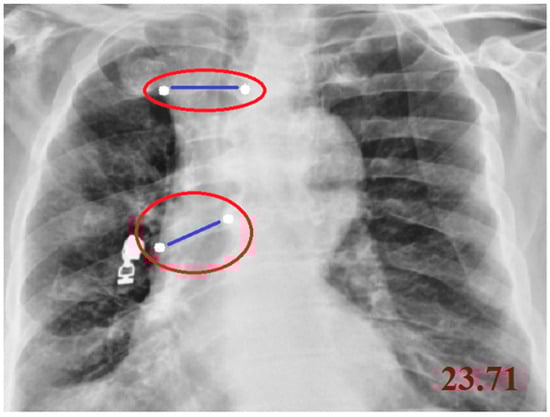

| Cobb Angle | cv2, numpy, math, tkinter | Measures vertebral tilt and spinal curvature angle | Calculated using four manually selected points |